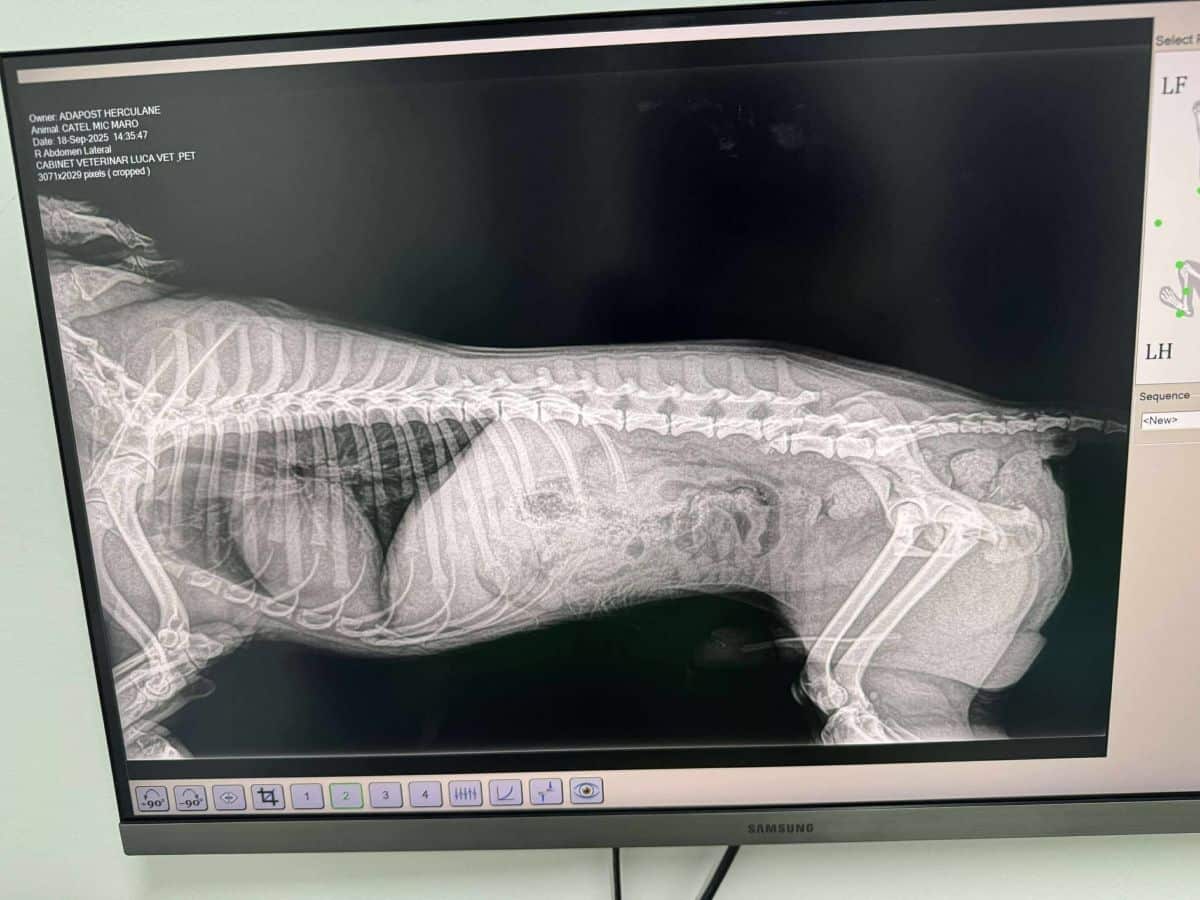

Hatte Autounfall (09/25)

Der goldfarbene THALES mit seinem lockigen Fell hatte leider einen Autounfall. Er wurde sofort in eine Tierklinik gebracht und operiert. Die größere Wunde am Rücken ist am Heilen.

Seine Hinterläufe sind nicht gelähmt, er kann sie benutzen, benötigt jedoch Physiotherapie und regelmäßige Übungen, um sie weiter zu stärken. Zurzeit bewegt er sich noch überwiegend auf den Vorderbeinen fort. Er ist nicht inkontinent und kann selbstständig urinieren.